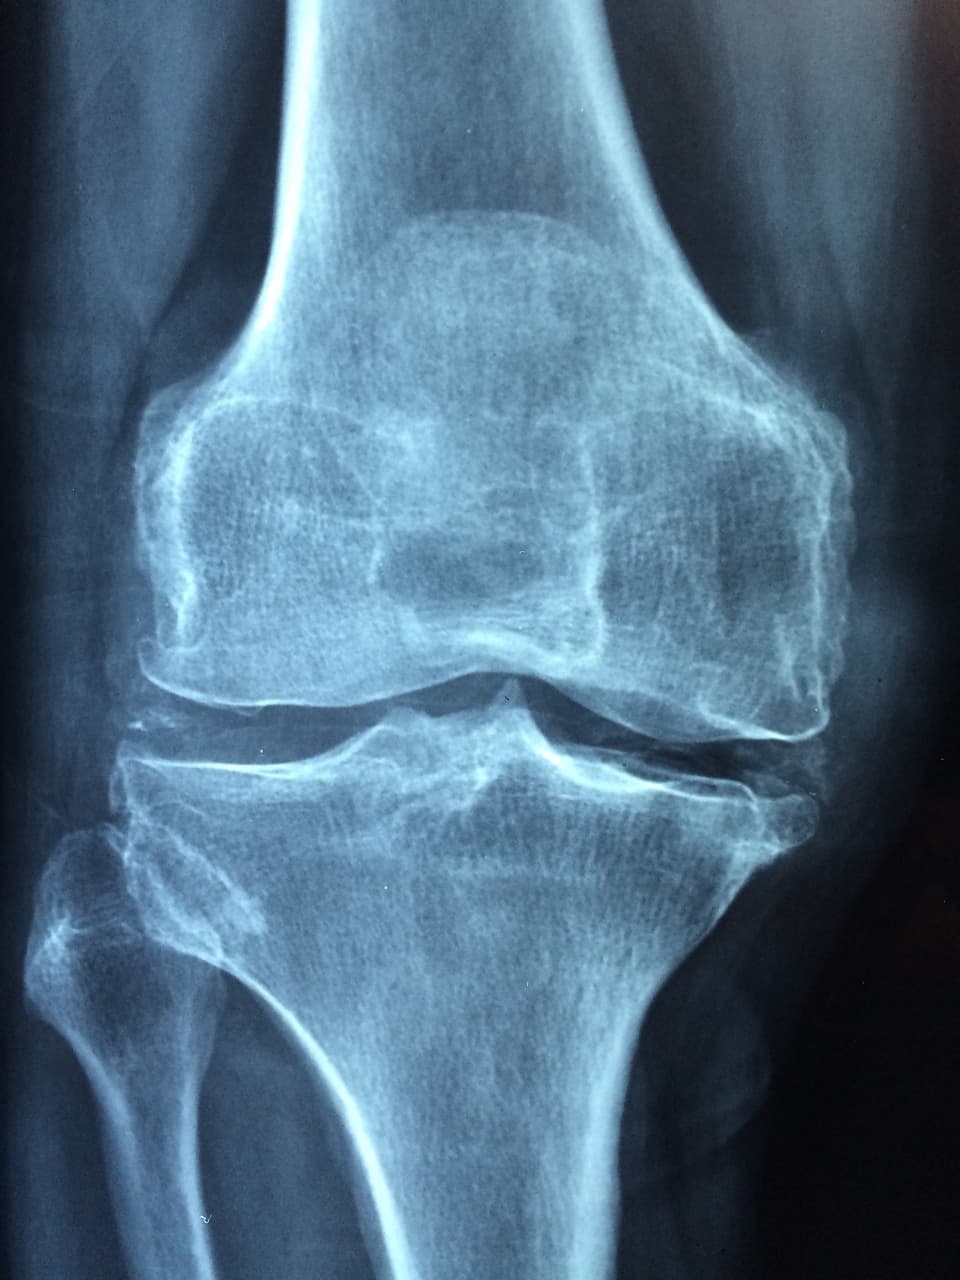

어머니는 60대 중반으로 평소 관절 통증을 호소하셨고, 어느 날 정형외과에서 골밀도 검사를 권유받아 검사를 받았다. 검사 결과는 ‘경증 골다공증’, 즉 T-Score가 -2.3 수준으로 확인됐다. 의사는 칼슘 보충과 함께 비타민 D, K2, 마그네슘 등의 복합 섭취를 추천했다.